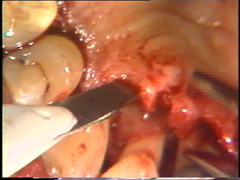

Aquí el defecto en la superficie de la raíz del central es claramente visible. Todo el tejido de granulación ha sido eliminado y el cráter óseo fué remodelado. El colgajo debe ser ubicado apilcalmente al defecto de la raíz para evitar la acumulación de placa subgingival postoperatoria. |